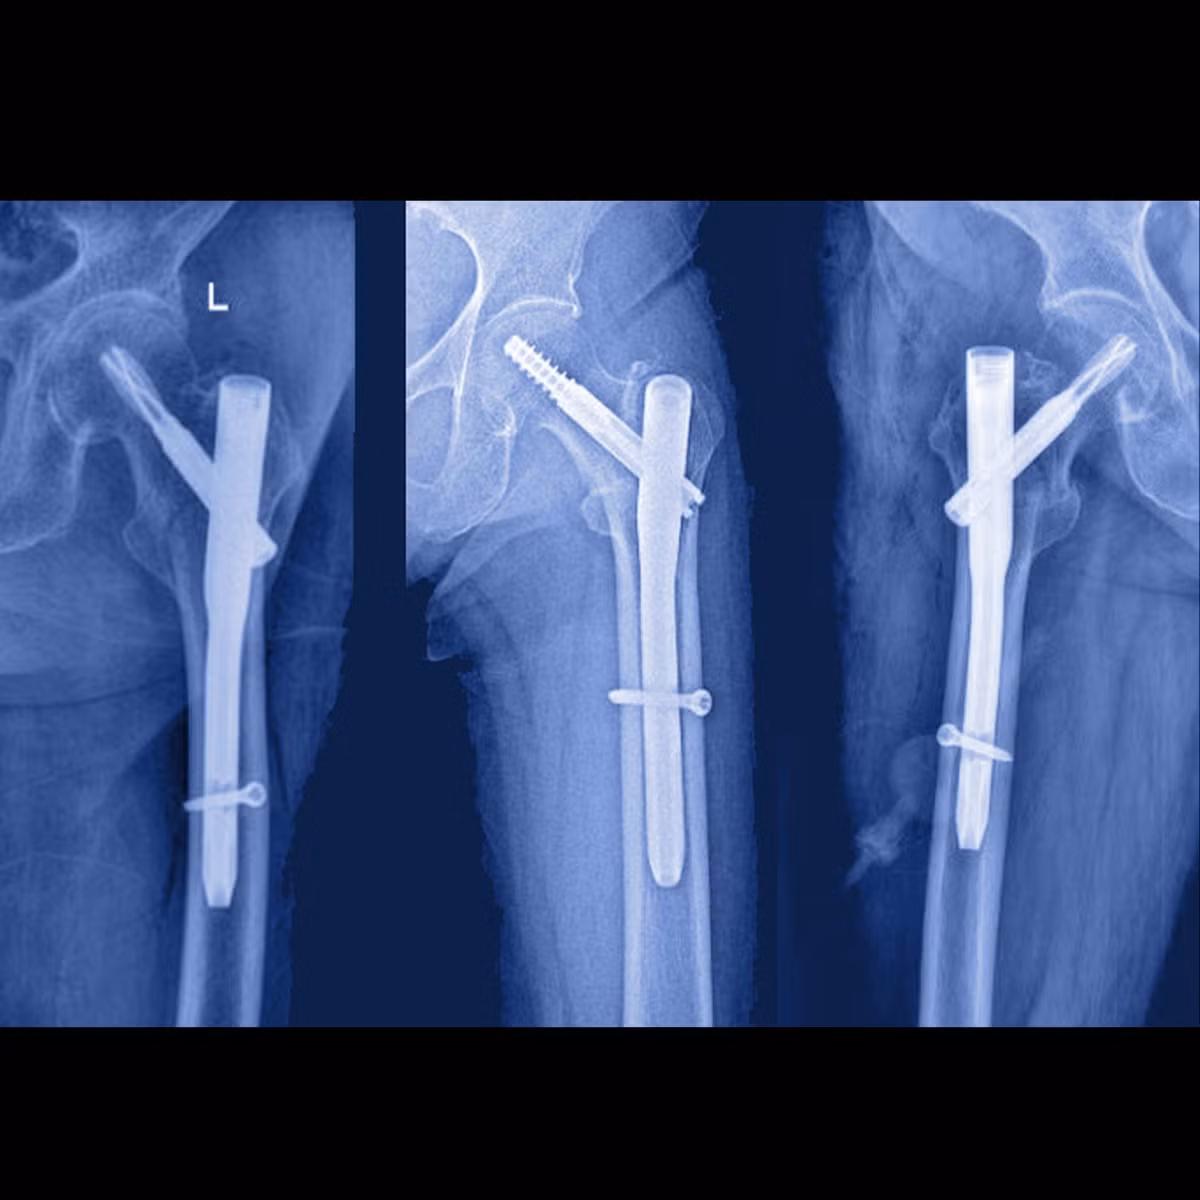

noi-xuong.jpg

Thăm khám cho bệnh nhân sau phẫu thuật - Ảnh BVCC

noi-xuong-1.jpg

Đóng đinh nội tủy bắt vít ổ gãy - Ảnh BVCC